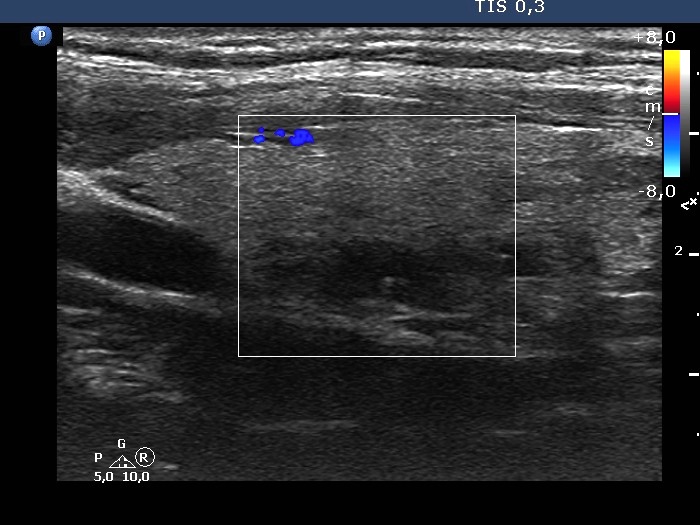

Left lobe, longitudinal scan, color Doppler mode. The lesion is avascular.